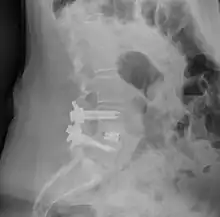

![]() Fusion of L5 and S1 | |

| Other names | Spondylosyndesis |